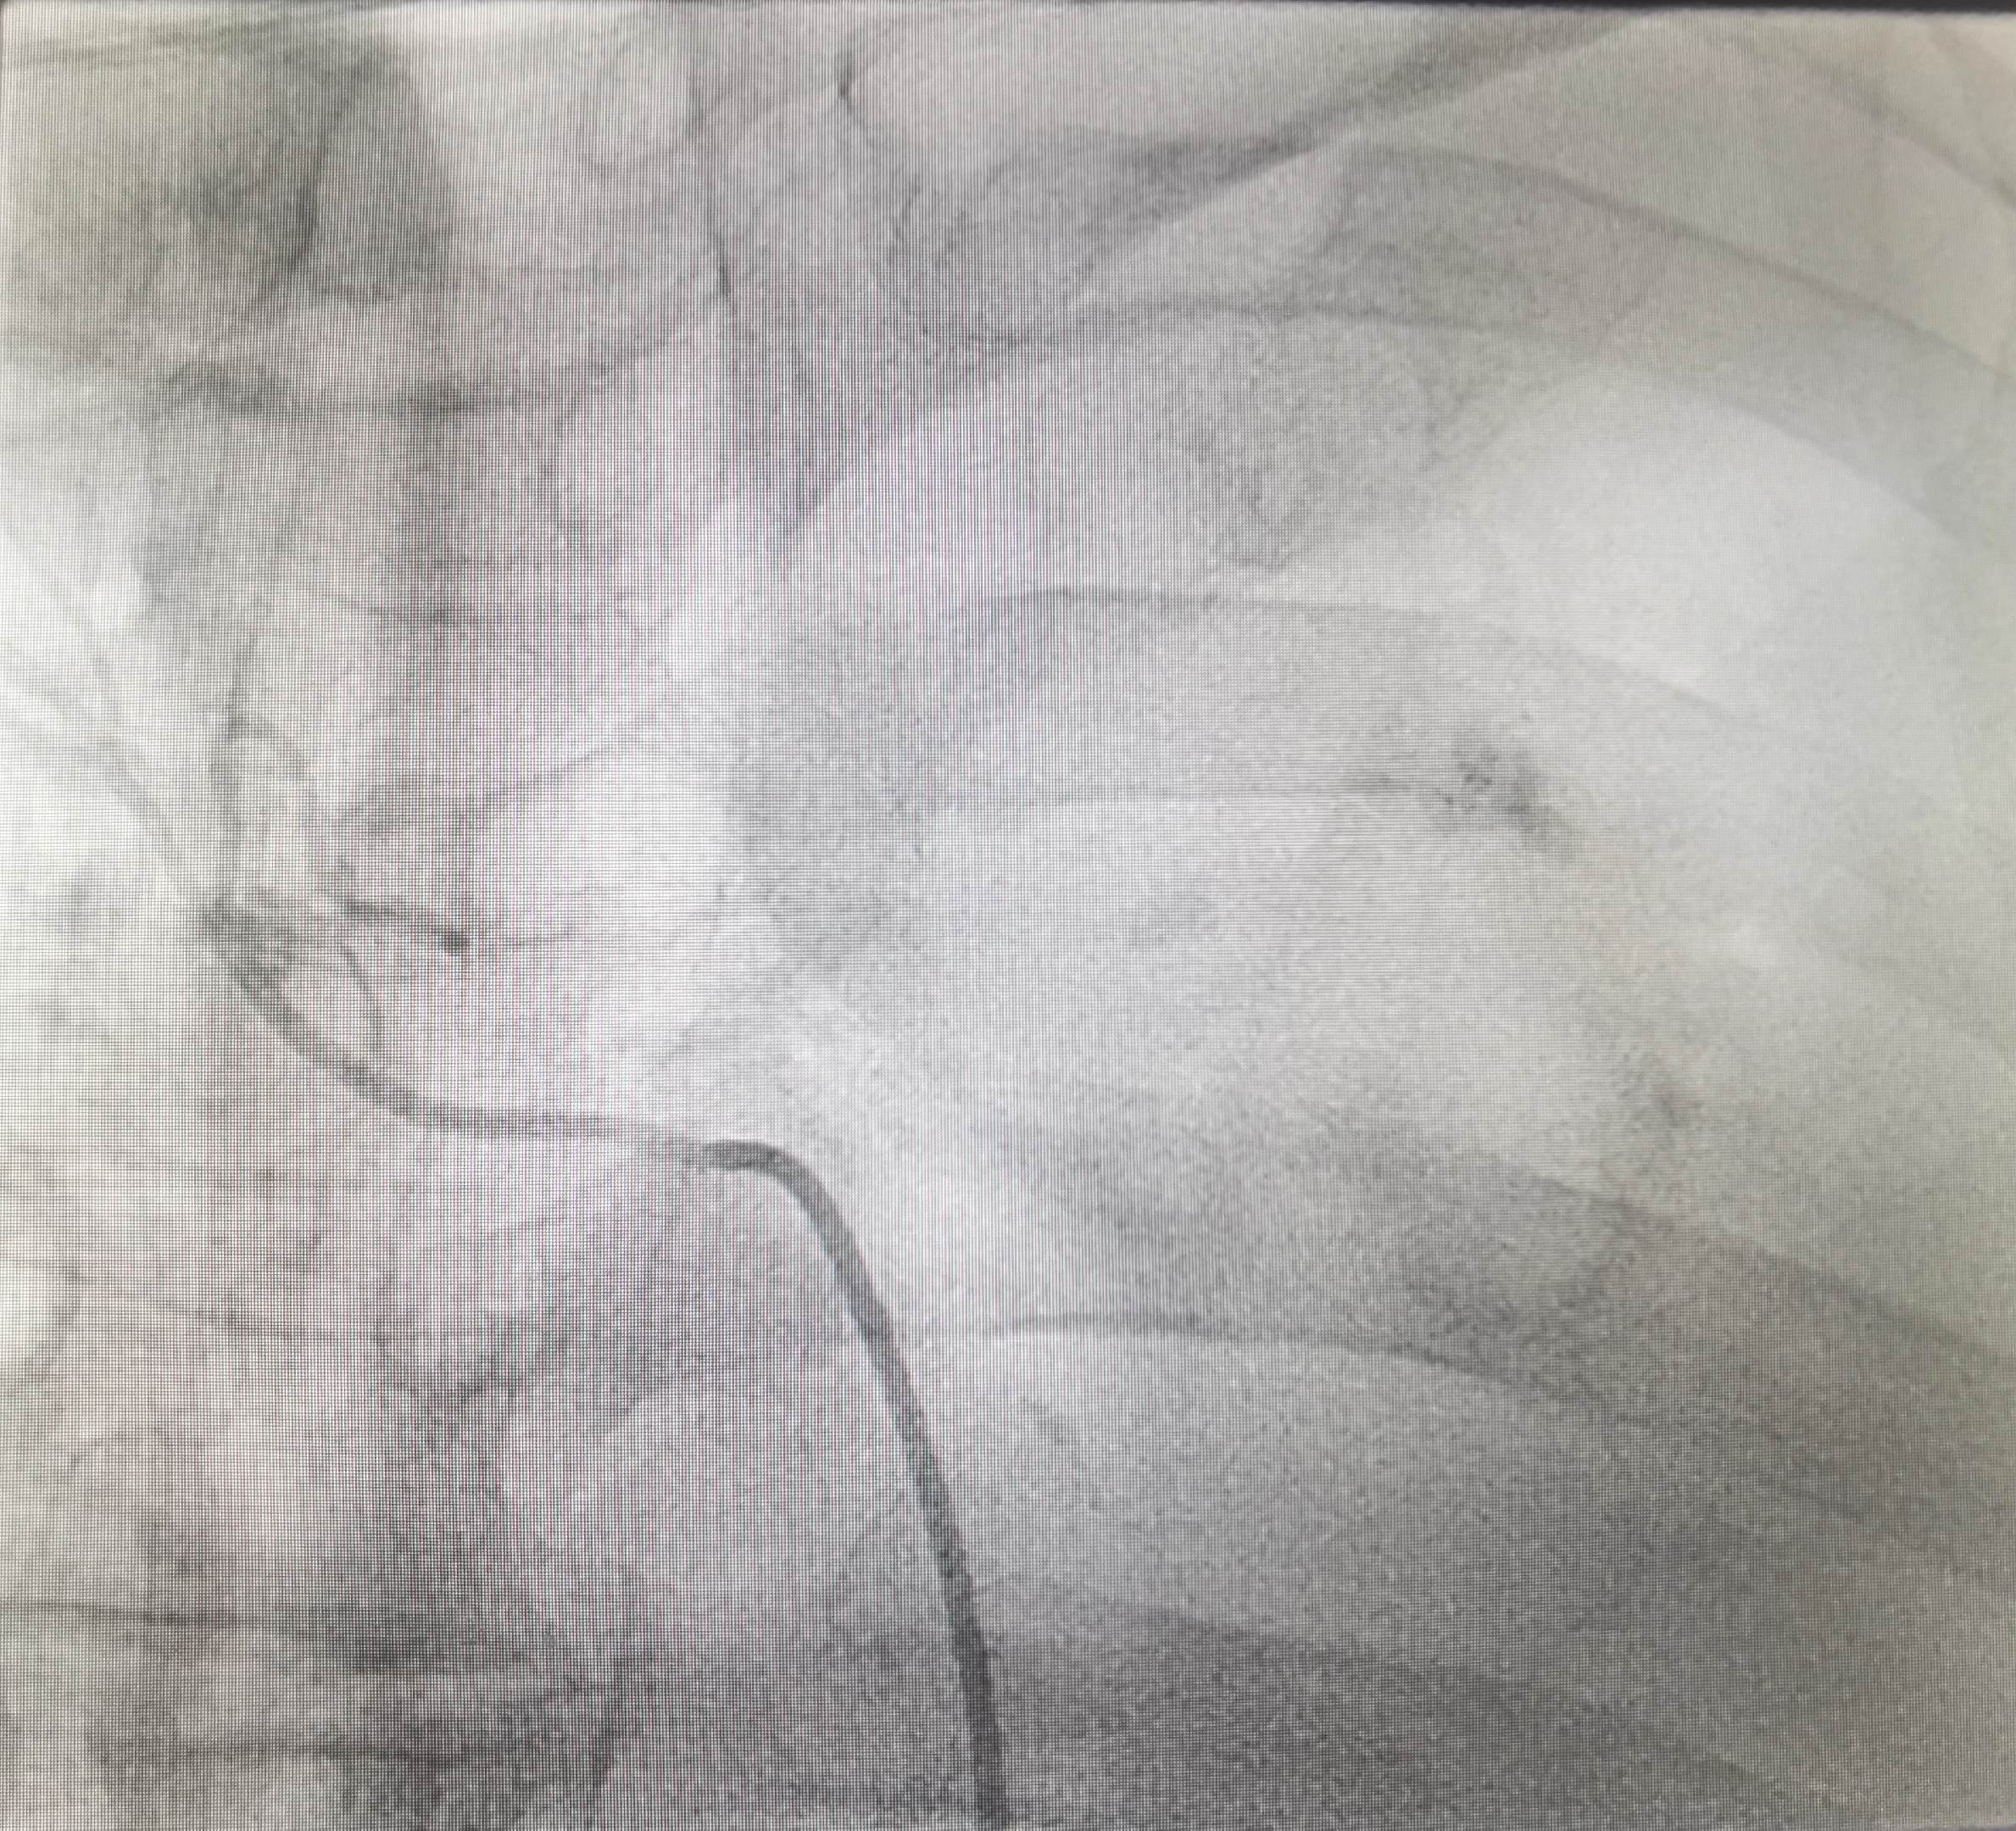

肺癌患者,左肺完全肺不张。经过一次bace的治疗,一个月后复查CT左肺完全复张,为后续全身治疗提供条件